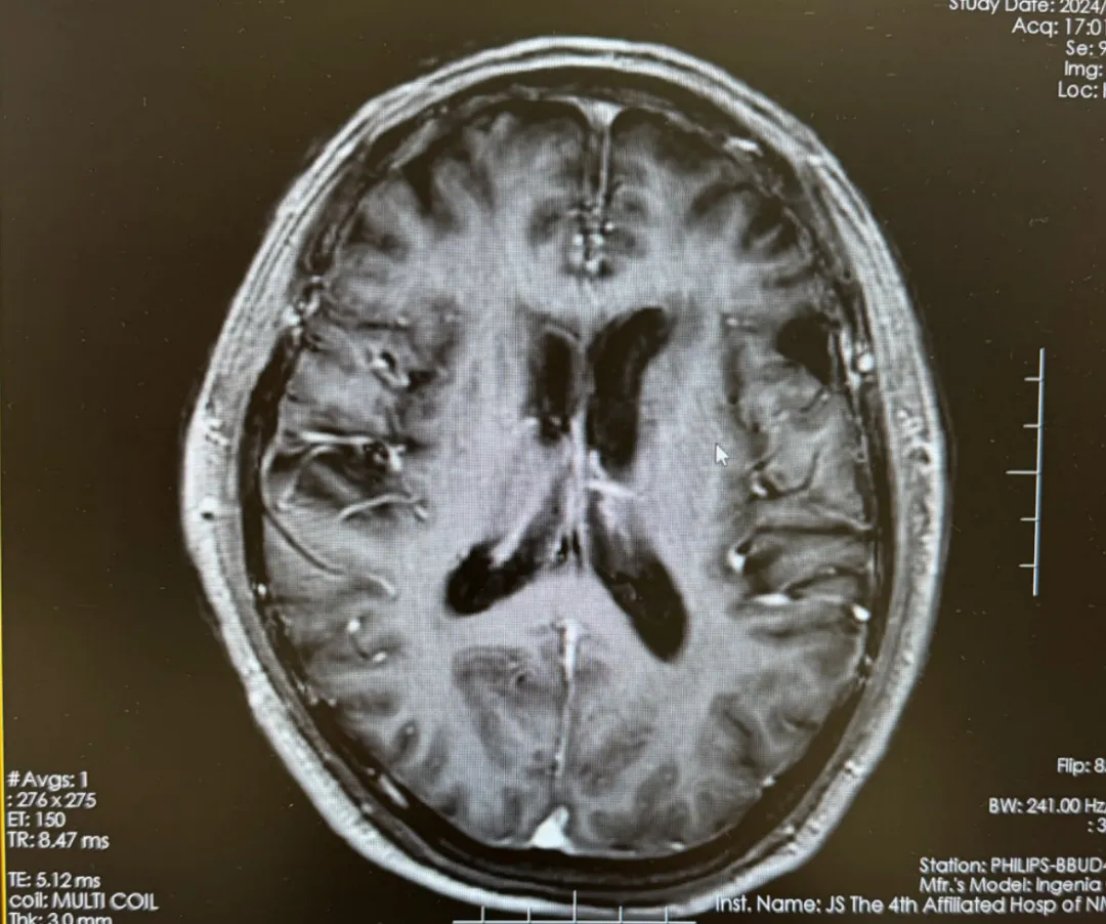

- 治疗2周期后:复查头颅MRI显示,脑内肿瘤已显著缩小至约1.7cm*1.7cm,周围水肿也明显减轻。

图2 化疗2周期后复查影像